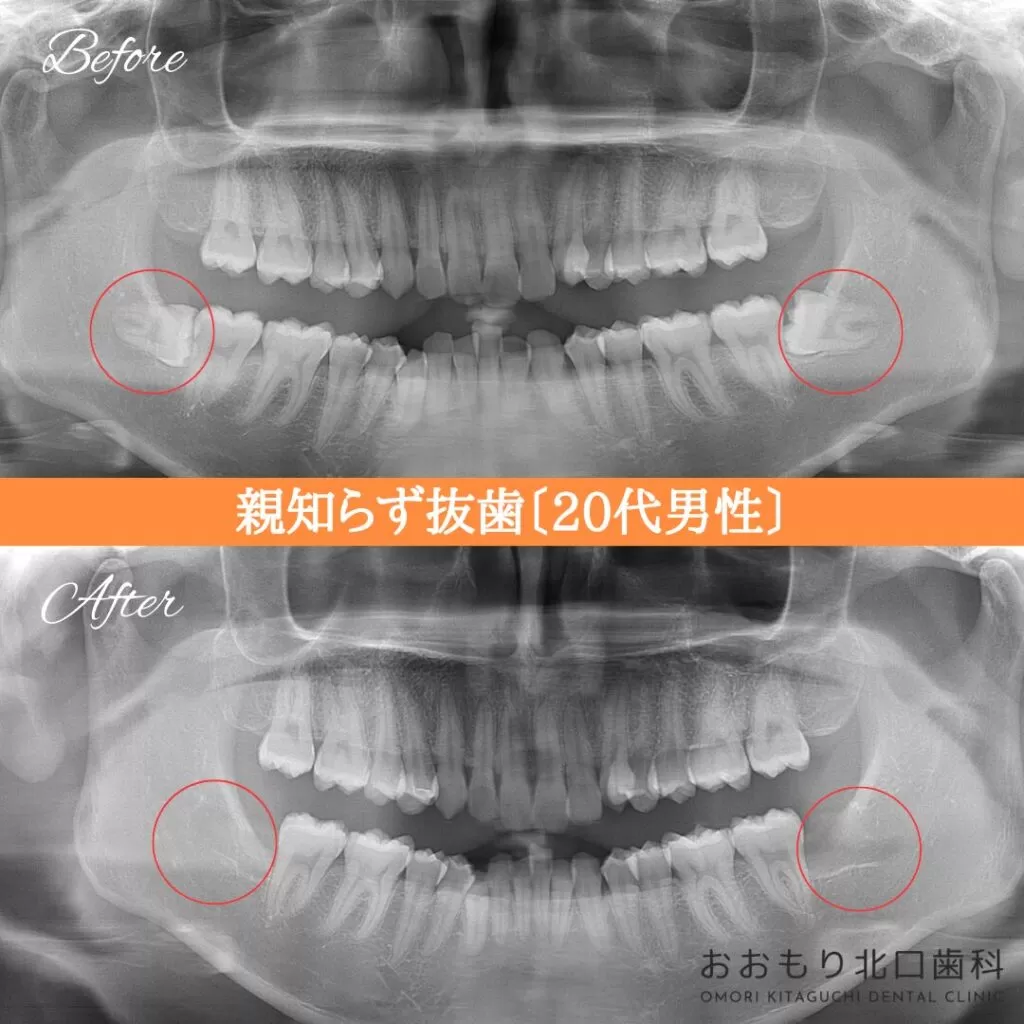

症例紹介㊺親知らず抜歯(20代男性)

本日は「親知らず抜歯」を行われた患者さまのビフォーアフターをご紹介します。

【治療名】親知らず抜歯

【患者さん】20代男性

【費用(税込)】保険治療

【リスク】 親知らずの抜歯は、手術中は麻酔により痛みを感じることがほとんどありません。

しかし、麻酔が切れた後には、時には腫れや痛みが発生することがあります。